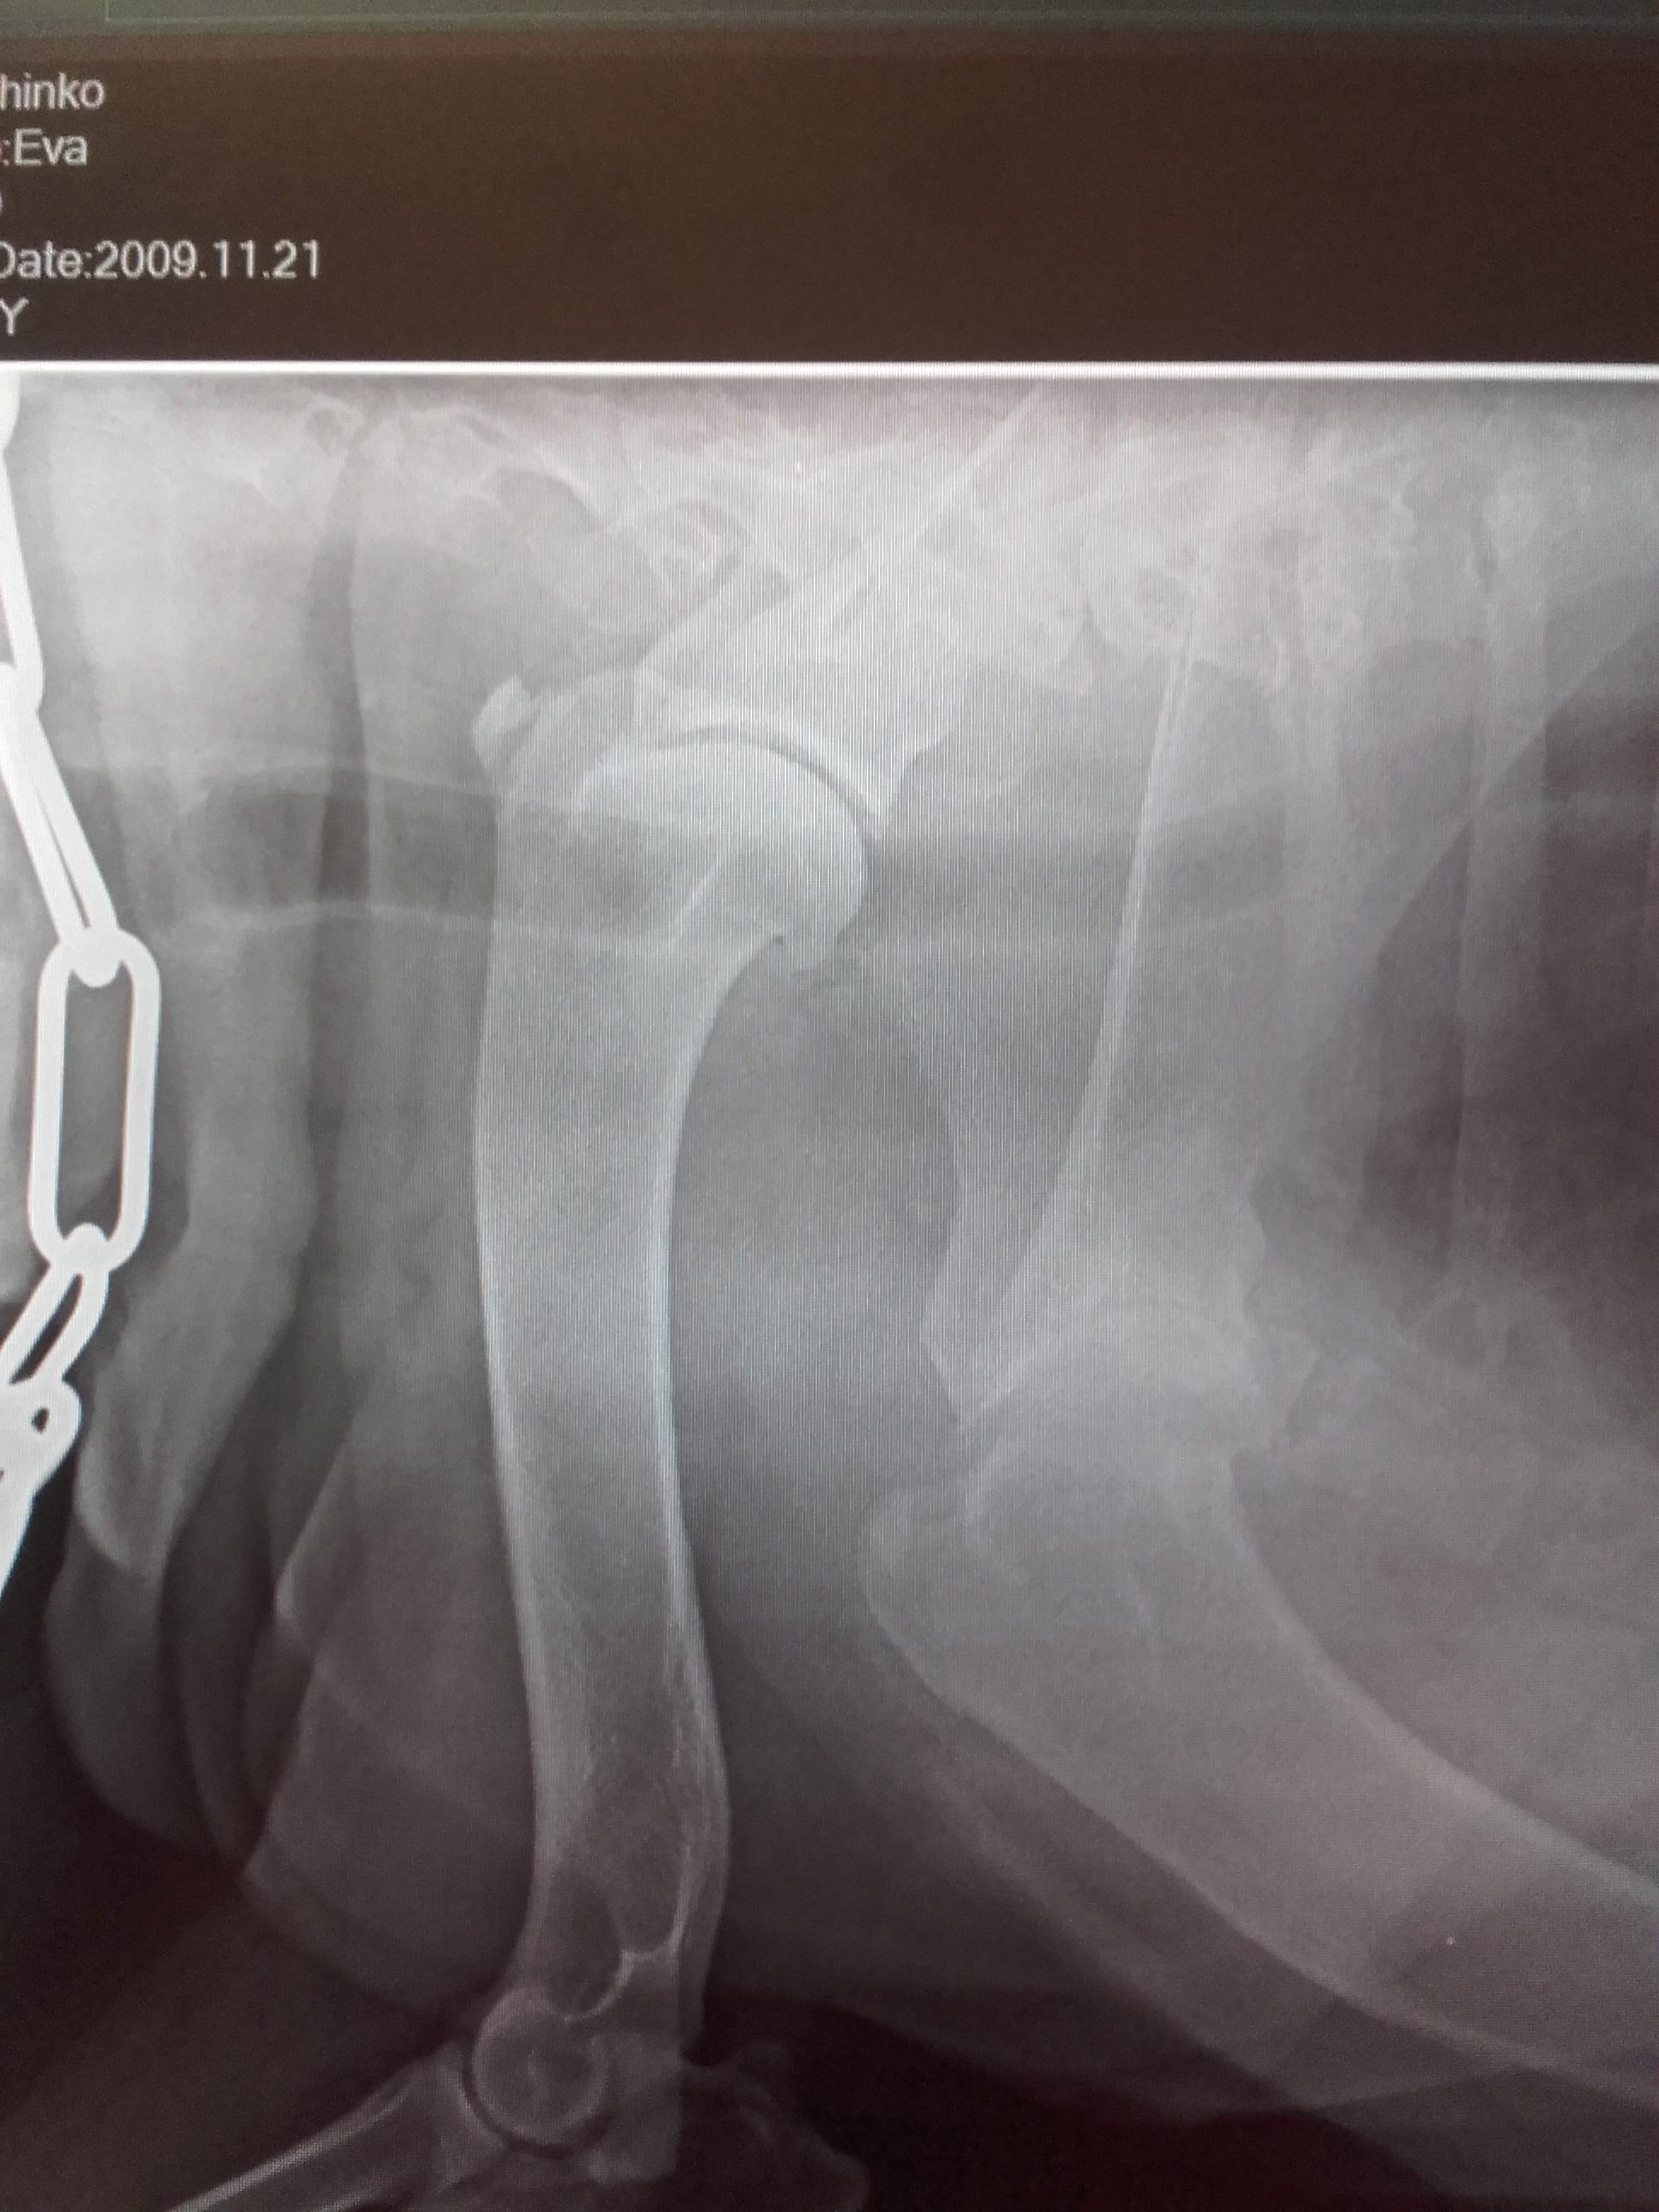

- Arthrosen im Schultergelenk eines Hundes.